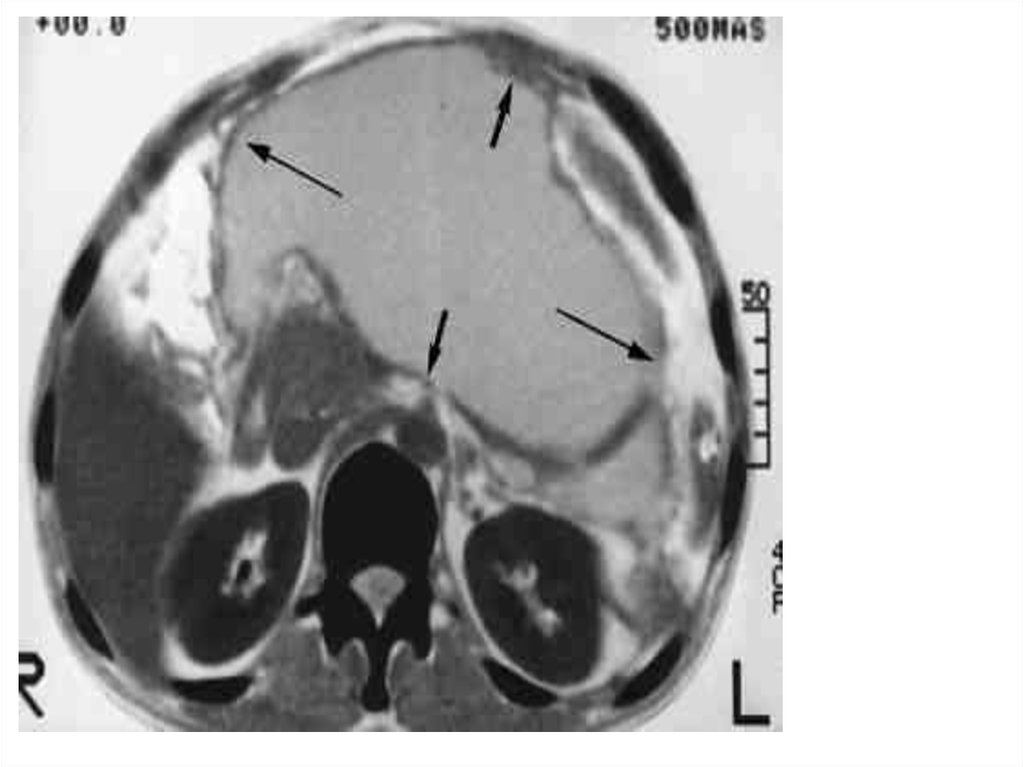

В сосудистой программе

при компьютерной томографии выявлена псевдоаневризма селезеночной

артерии (1,0 х1,5 см), прилежащая к псевдокисте